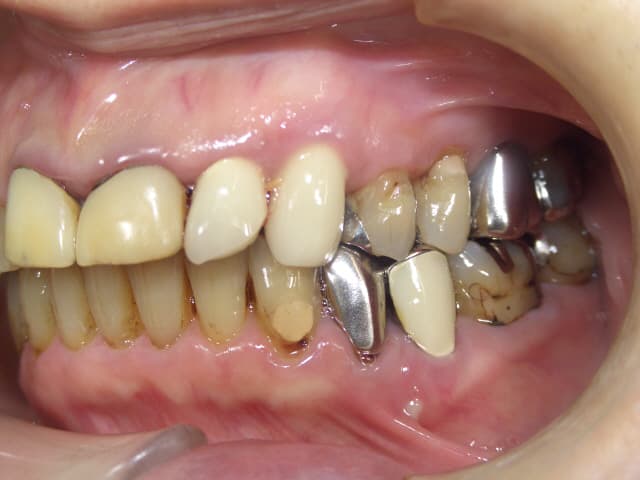

今回ご紹介する歯周治療のケースは、70代女性の方です。

歯周病は中等度で、歯ぐきの腫れや出血(BOP 80%以上)、口臭がありました。

また、被せ物も古くなり歯ぐきとの境目に段差が出来てしまい、2次虫歯も多く確認できました。